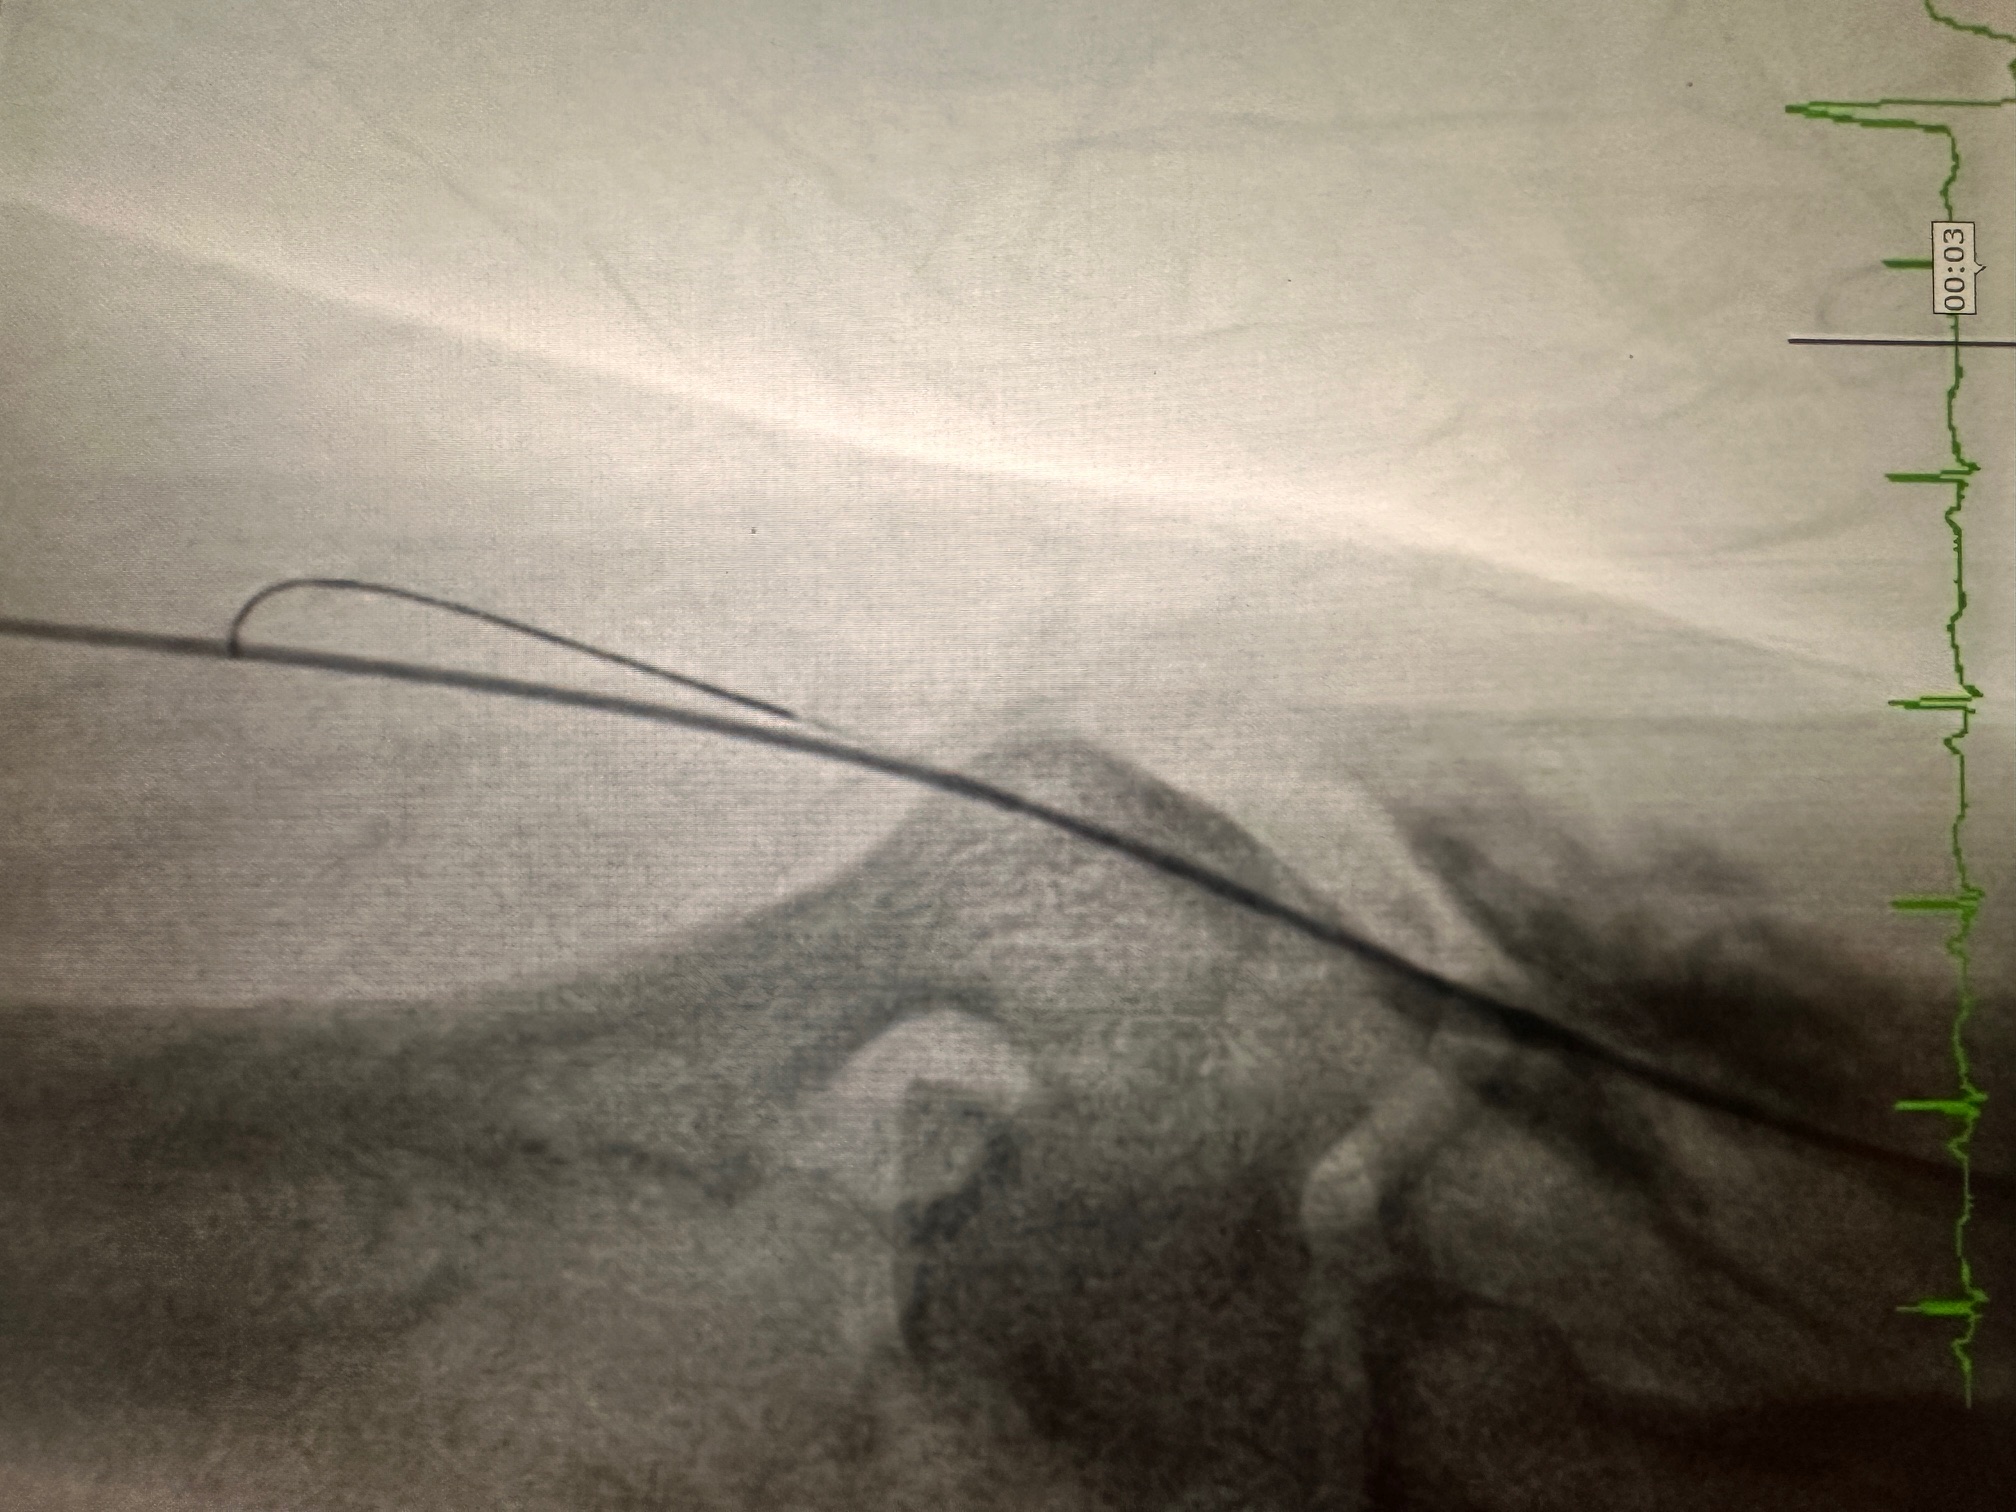

- Wire Navigation:

- Advanced a 0.035-inch guidewire into the aorta through the perforated radial artery.

- Introduced a 0.014-inch coronary wire alongside the 0.035-inch wire to maintain distal radial and aortic access for stabilization.

- Balloon-Assisted Technique:

- Positioned a 2.0 mm semi-compliant balloon at the edge of the guiding catheter within the radial artery.

- Inflated the balloon slightly to dilate the perforated segment, facilitating the guiding catheter's smooth passage through the radial artery into the ascending aorta.

- The technique minimized trauma while maintaining radial flow.